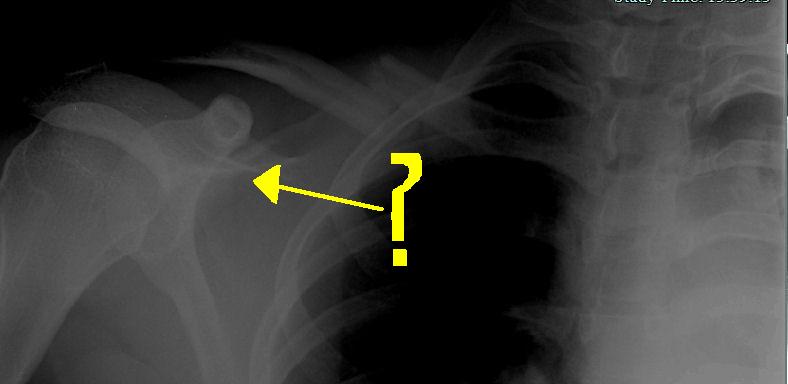

OK, here's a screenshot. The app allows you to adjust the brightness and contrast, so I've messed with it to show the break as best as possible, so that's why the rest of the x-ray looks weird. The pain right now is not bad at all, even with no painkillers.

The x-ray pics are unfortunately embedded in the application, so I can't show you guys. But it's very broken - the piece attached to my shoulder has dropped under the other piece, so it's not just bent.

Clavicle isn't too bad. Did yours break all the way in two or just get "bent" like mine?